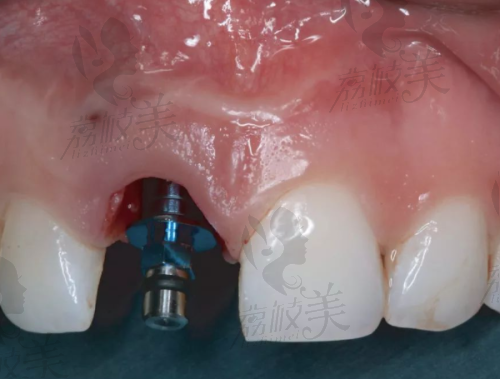

首先,卡尔斯可不是“空降网红”,而是货真价实的“种植牙老牌大佬”。它起源于德国,继承了德系工业一贯的精细与严苛标准。整个种植体系统从设计、材质到加工制造,全都满满高新科技,“仿生结构 + 四重表面处理技术”,稳定性好到想给它竖大拇指。

BioActive仿生设计模拟天然牙齿根部结构形态更贴合牙槽骨,长期稳固不松动

四重表面处理技术等离子喷砂 + 微孔腐蚀技术更容易跟牙骨融合,提升成功几率

纯钛材料(美标 Grade 4)稳定性强、不过敏、超强耐腐蚀降低排异反应,对金属过敏者也友好

短小体积适配狭窄牙槽小尺寸设计,较大限度保留原生牙结构骨量不足人群也可尝试种植